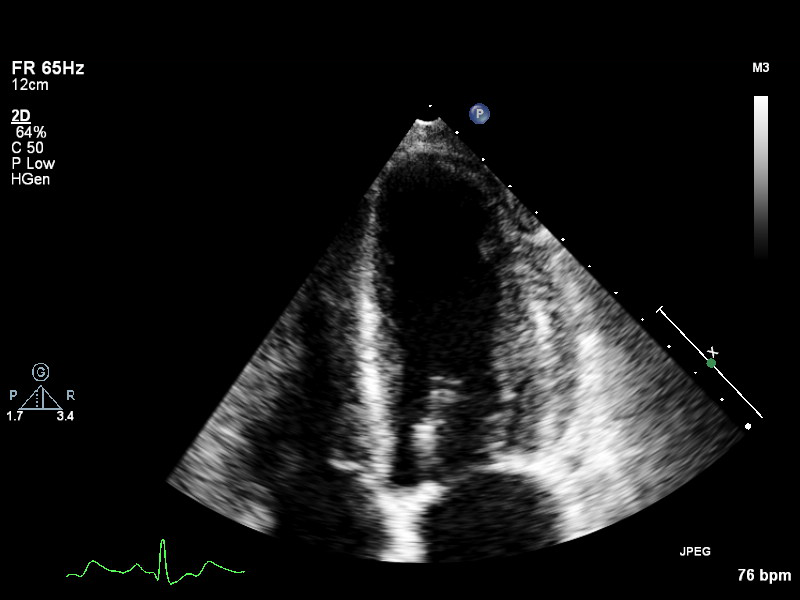

plax-full-la plax-full-la Parasternal long-axis, sector covers whole LA; intended for LA measurements